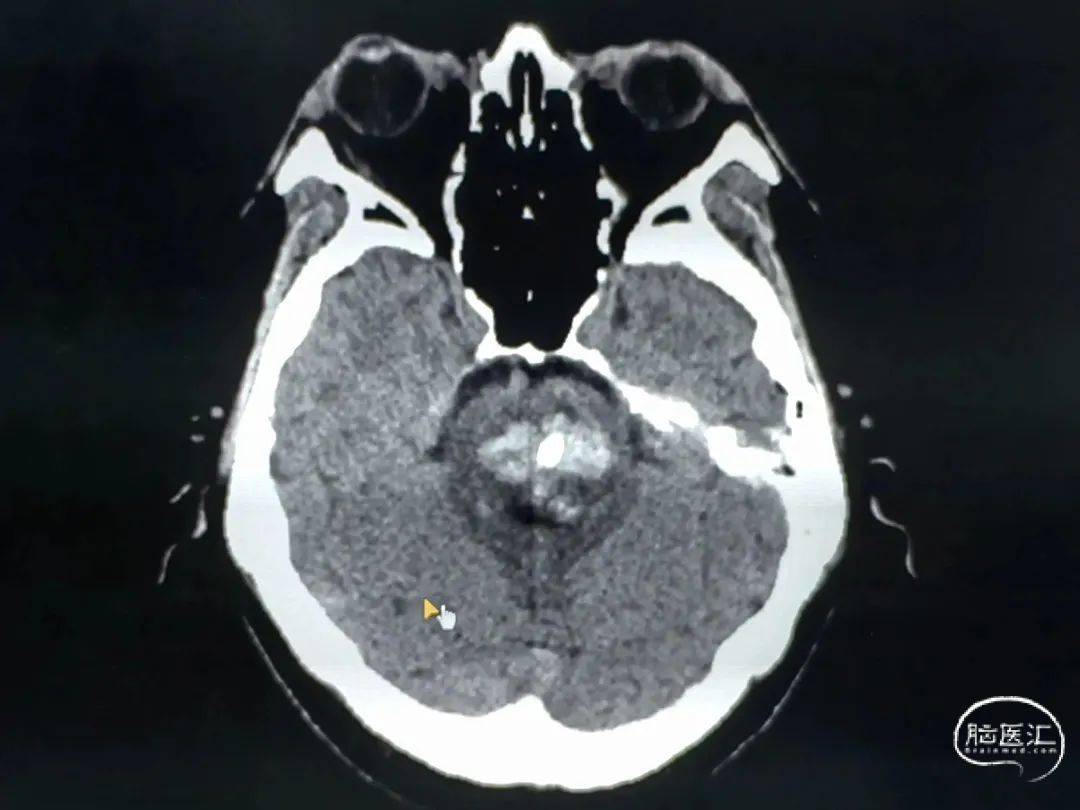

对血肿层面较少、面积较大,主要位于桥脑中下部的血肿,选择幕下经小脑半球-小脑中脚-桥脑入路;

CT扫描后测算脑干血肿穿刺靶点及路径

术后尿激酶应用,术后3天复查CT,血肿引流满意